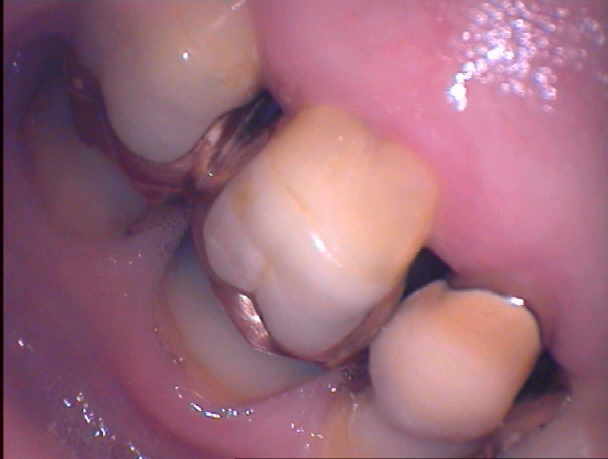

Die Patientin kam wegen eines vestibulären PAR-Abszesses an 26 bei exzellenter Mundhygiene, die eigentlich besser nicht sein könnte. Im Bild sind die bukalen Abhänge von 26 schon deutlich eingeschliffen. Wenn man bedenkt, wie lange diese Arbeit bereits benutzt wird, kann man sich vorstellen, wie diese Abhänge einmal ausgesehen haben als sie neu waren.

Jetzt schauen Sie mal, wie die Zähne nach 20 Jahren von vestibulär ausschauen. Jetzt kann man sich vorstellen, dass eine Aufbiss-Schiene sicher die bessere Therapie gewesen wäre als ein gnathologisch-technischer Rundumschlag.

Beim nicht forcierten Schlussbiss zeigt sich eine sehr konkrete Verzahnung mit unauffälligen Kontaktpunkten. Legt man jedoch den Zeigefinger auf die vestibulären Zahnflächen und drückt leicht nach innen (und damit die gelockerten Seitenzähne in ihre physiologische Lage), so sieht man die dicken Fehlkontakte auf den ausgeprägten bukalen Abhängen, auf denen die Patientin zuerst aufkommt, um dann an ihnen herunter in die Zentrik zu gleiten, wobei die Seitenzähne seitlich nach vestibulär ausweichen müssen. Die Lockerungsgrade und die “langen Zähne” sind die logische Folge.

In diesem Fall sind die Abhänge ja nicht einmal maximal aufgewachst. Häufig sieht man noch wesentlich ausgeprägtere, jugendlichere Kauflächen. Bei Patienten mit neuen Kronen, die kältempfindlich bleiben, finden sich häufig Frühkontakte auf solchen Abhängen. Wenn sie noch steiler aufgewachst sind, sind diese extrem schwierig zu erkennen, da sie sehr punktförmig sind. Häufig erkennt man sie erst, wenn man aus der klinischen Erfahrung heraus ex juvantibus leicht abflacht und dabei aufrauht.